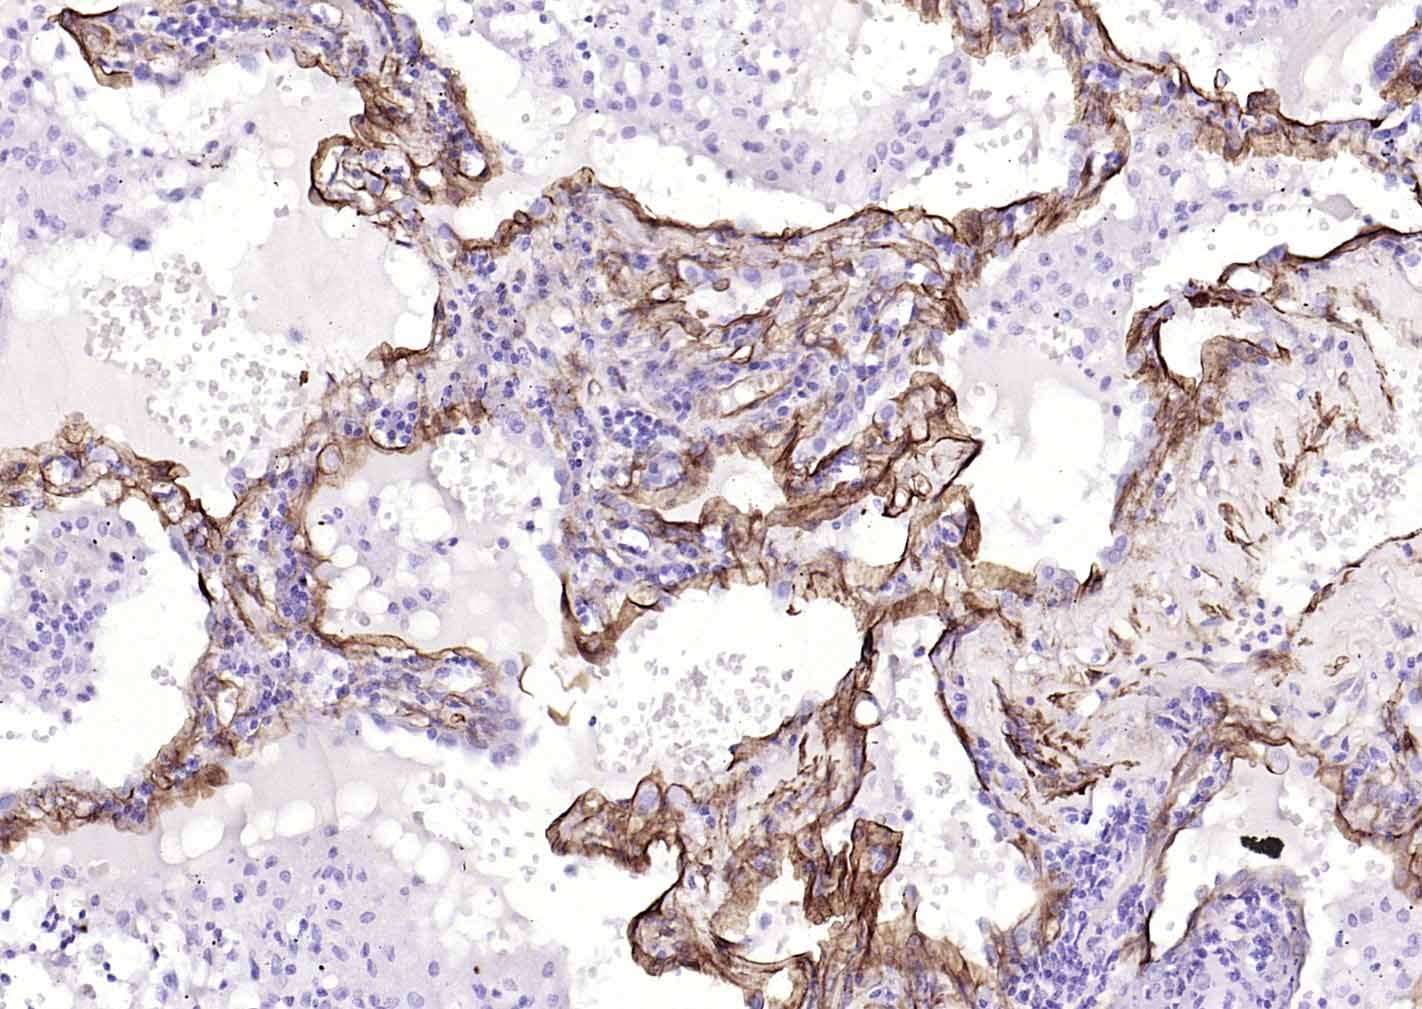

Paraformaldehyde-fixed, paraffin embedded (human lung carcinoma); Antigen retrieval by boiling in sodium citrate buffer (pH6.0) for 15min; Block endogenous peroxidase by 3% hydrogen peroxide for 20 minutes; Blocking buffer (normal goat serum) at 37°C for 30min; Incubation with (Caveolin-1) Monoclonal Antibody, Unconjugated (bsm-60809R) at 1:500 overnight at 4°C, followed by operating according to SP Kit(Rabbit) (sp-0023) instructionsand DAB staining.